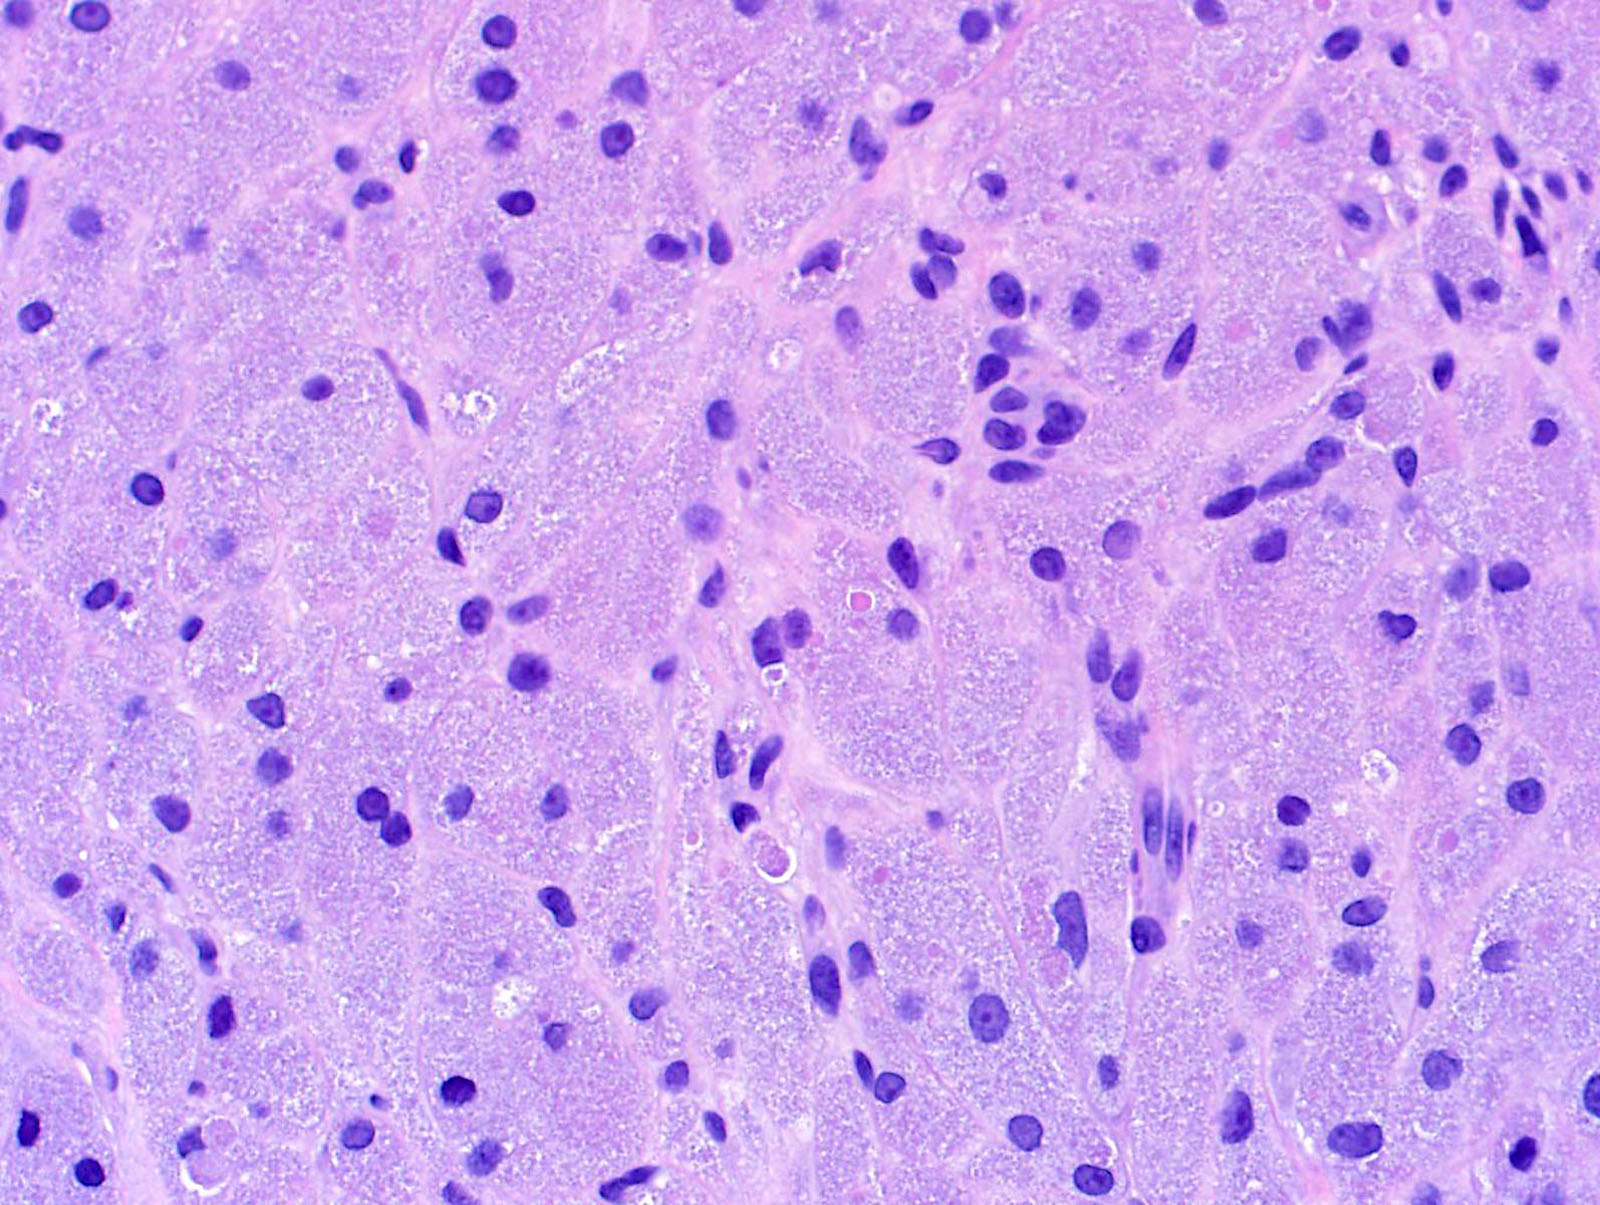

Microscopic (histologic) description

- Large polygonal cells with abundant eosinophilic granular cytoplasm and small, central nuclei

- Nonneural granular cell tumors (S100-) can exhibit nucleomegaly, pleomorphism and variable mitotic activity (Am J Surg Pathol 1991;15:48, Histopathology 2005;47:179)

Microscopic (histologic) images

Contributed by Jarish Cohen, M.D., Ph.D.

- Skin, left thigh, shave biopsy:

- Nonneural granular cell tumor (see comment)

- Comment: The biopsy shows a polypoid mass of large, oval cells with ample pallid and both finely and coarsely granular cytoplasm, with some pustulo-ovoid bodies. The lesional cells are S100 negative, MITF negative and NKI-C3 strongly positive. An ALK immunostain shows moderate patchy positivity. A phosphohistone H3 shows that cells in mitosis are exceedingly rare, under 1/mm2. The histopathologic and immunohistochemical findings are consistent with nonneural granular cell tumor (also known as primitive polypoid granular cell tumor).